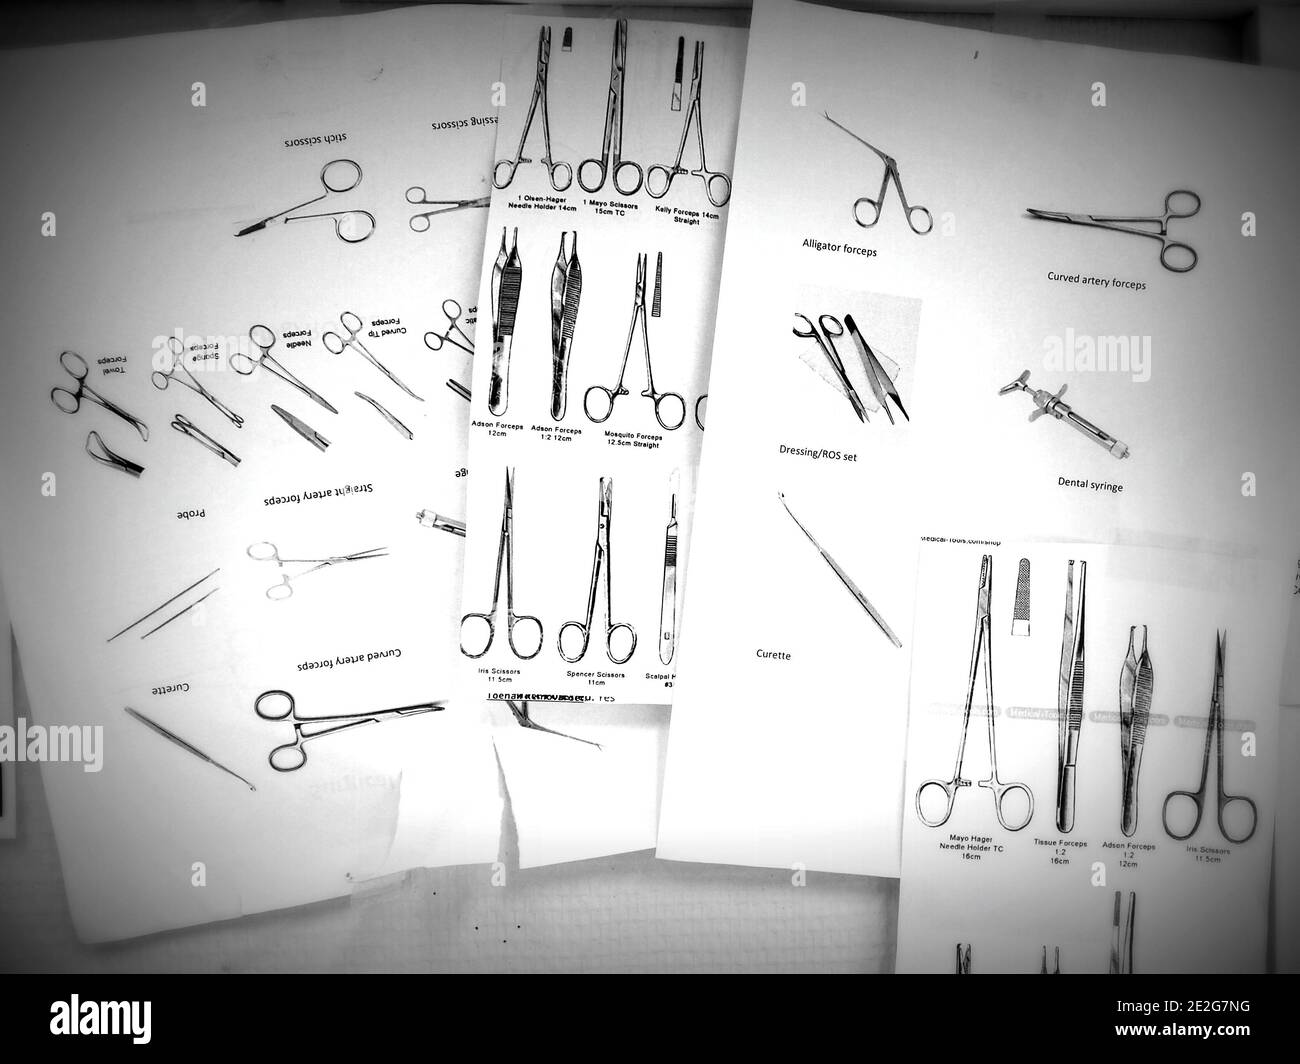

Papiere auf einer Stiftleiste in einem medizinischen Zentrum, die Arten von Scheren und Pinzetten benennen, die von Krankenschwestern und Ärzten verwendet werden Stockfotohttps://www.alamy.de/image-license-details/?v=1https://www.alamy.de/papiere-auf-einer-stiftleiste-in-einem-medizinischen-zentrum-die-arten-von-scheren-und-pinzetten-benennen-die-von-krankenschwestern-und-arzten-verwendet-werden-image397425100.html

Papiere auf einer Stiftleiste in einem medizinischen Zentrum, die Arten von Scheren und Pinzetten benennen, die von Krankenschwestern und Ärzten verwendet werden Stockfotohttps://www.alamy.de/image-license-details/?v=1https://www.alamy.de/papiere-auf-einer-stiftleiste-in-einem-medizinischen-zentrum-die-arten-von-scheren-und-pinzetten-benennen-die-von-krankenschwestern-und-arzten-verwendet-werden-image397425100.htmlRF2E2G7NG–Papiere auf einer Stiftleiste in einem medizinischen Zentrum, die Arten von Scheren und Pinzetten benennen, die von Krankenschwestern und Ärzten verwendet werden